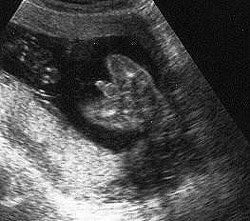

الولد

ولد في الأسبوع ال 15